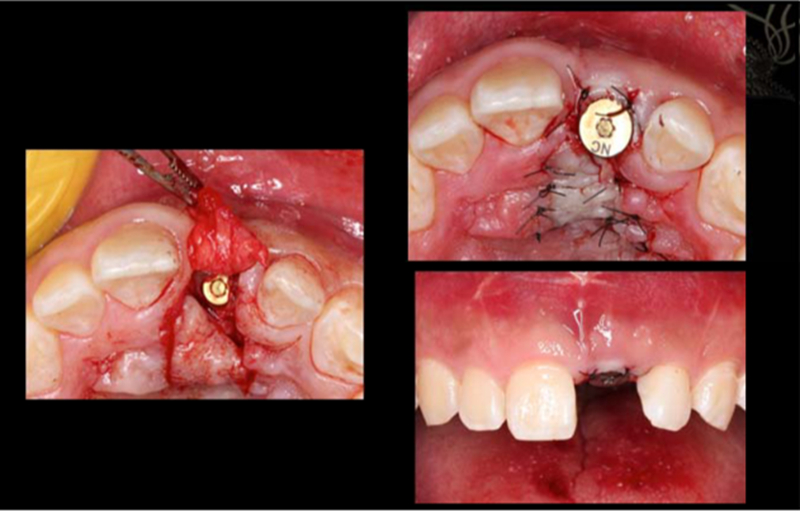

二期修復,放入愈合基臺

1.使用螺絲固位修復方案 2.軟組織恢復效果佳,達到美學效果

術(shù)后照片